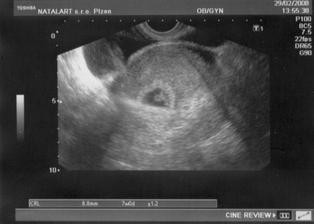

29.2- další velké nervy, čekání na srdíčko - na UTZ byla vidět krásná srdeční akce, Zdenda byl se mnou v ordinaci a měli jsme obrovskou radost!!!...jsme nyní na začátku 8.tt (7+0) - to je ještě dlouhá cesta....